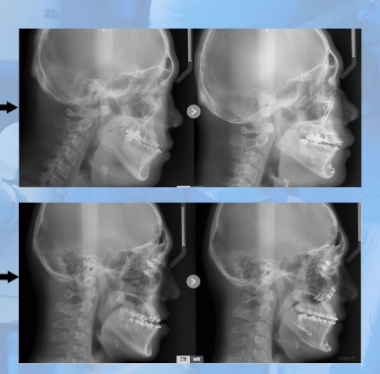

Page 61 - 艾美综合整形_Neat